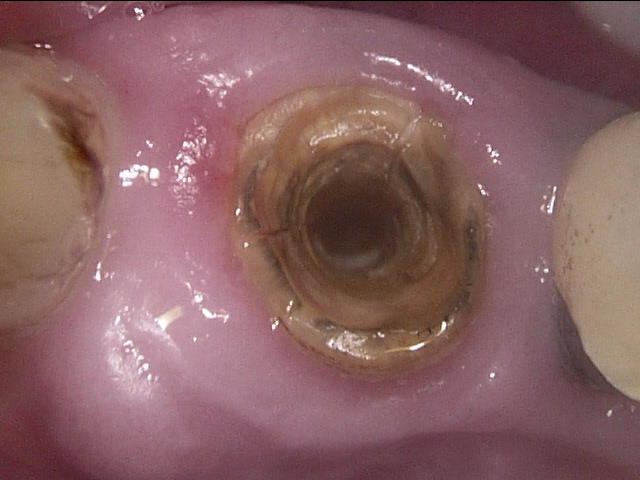

この歯を実際にお口の中で見ると、こういう風に見えます。

解説します。

赤丸の部分の歯ぐきが腫れています。矢印の部分は歯の縦に亀裂が入った様子が見られます。

この歯は大きい奥歯で、根が3本ありますが、そのうちの1本が折れており、他の2本もダメージがかなり大きかったので、無理に残しても数年持つかどうかという状態でした。

患者さんとよく話し合って、抜歯することになりました。